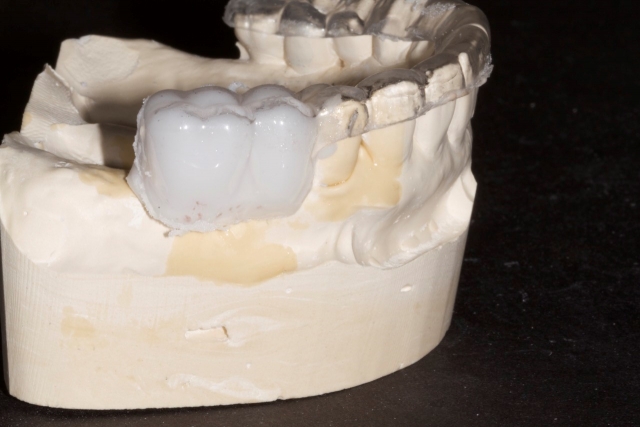

5. Using a radiopaque self-curing methylmethacrylate mixed to a putty consistency, fill the space left by the denture teeth or wax-up.

6. Trim the excess acylic back to the gingival margins.

7. Spot the desired exit point of the implant platform on occlusal surface of the teeth.

8. Using a 2 mm twist drill or disposable implant drill cut a hole through the acrylic until the drill touches the stone model.

9. Clean up the edges using an acrylic finishing bur.

10. When tried in, the template should be solid and stable and have a “snap-fit.”

The patient can be instructed in how to insert the appliance and can take it with them if they are having the CBCT done outside of your office. The end result will give you and the surgeon a more clear understanding of potential implant positions. The hole that is drilled through the teeth will be radiolucent on the CBCT and serve as an indicator of possible implant angulation that can be corrected by the surgeon as the case is planned.

If the CBCT exam shows that the proposed position is acceptable and that no grafting is needed, this radiographic guide can be converted to a surgical guide by simply inserting metal sleeves that are the appropriate diameter to the drills the surgeon prefers.